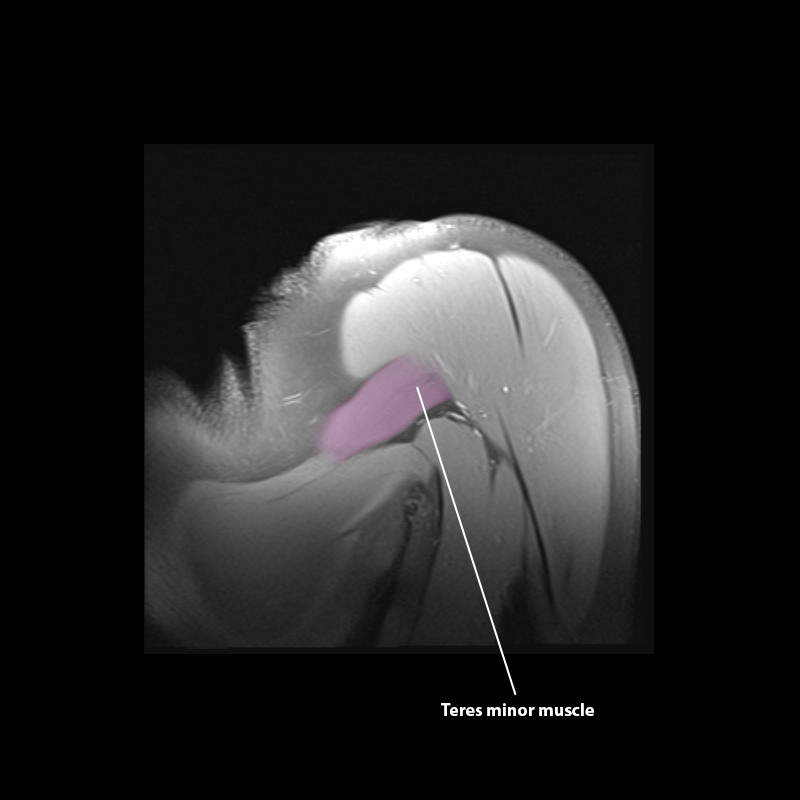

Shoulder MRI Anatomy